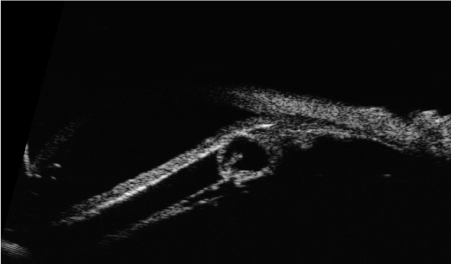

Ultrabiomicroscopy (UBM) examination of the right eye was performed with a 50 MHz probe and revealed a solid lesion of the ciliary body in the inferior-temporal quadrant and cysts with low reflectivity content. The cysts were behind the iris and surrounding the ciliary body. An initial cataract, resulting from the contact with the lesion was also noted. Left eye showed no alteration. Maximun thickness of the lesion, including sclera was 3.5 – 4 millimeters (mm) and the basal diameter was 7 mm (Figure 1). Patient was treated with Rutenium-106 plaque brachytherapy on December 20th, 2010 and 110 Gray (Gy) at the tumor apex was administered. Plaque was removed on December 23rd, 2010.

Figure 1. Ultrabiomicroscopy. the solid lesion of the ciliary body before treatment. The tumor pushing the lens caused cataract